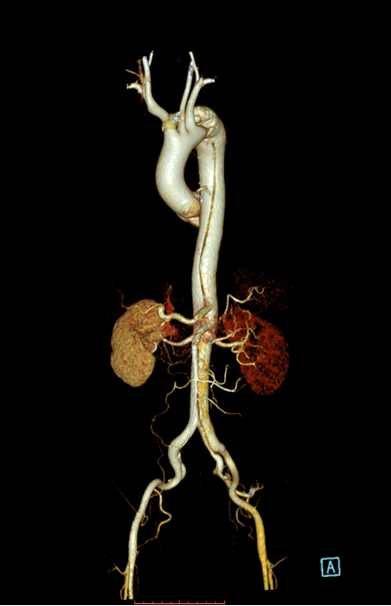

患者以“突发胸背部疼痛1月余”为主诉急诊入住中南大学湘雅二医院血管外科,入院后经过CTA确诊为“主动脉夹层”,夹层第一破口紧邻左锁骨下动脉,且左锁骨下动脉起始部呈局限性夹层样改变,胸主动脉真腔全程受压,病情十分危重,患者疼痛难忍!

术中通过DSA造影显示:主动脉夹层破口位于左锁骨下动脉近端,真腔压闭!舒畅教授为患者完美的实施TEVAR+左锁骨下动脉裙边烟囱支架置入术,手术过程非常顺利,胸主动脉支架释放良好,患者的主动脉夹层破口封闭良好,真腔打开良好,左锁骨下动脉释放的裙边支架血流通畅,没有内漏发生。

术前DSA

术后DSA